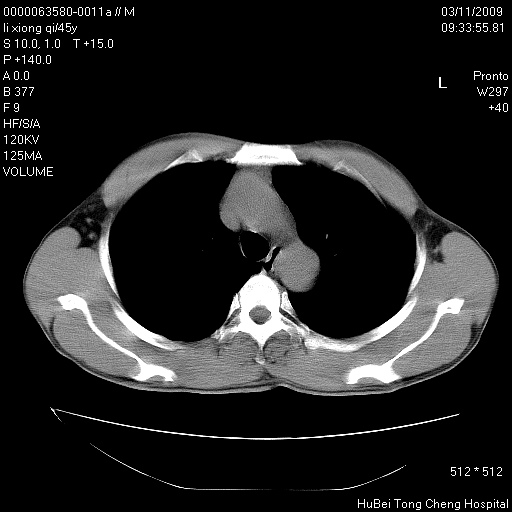

患者 男,45岁。胸痛,咳嗽伴痰中带血1月余。

临床诊断:肺结核?

胸部ct轴位平扫(层厚10mm,螺距1.5,重建间隔10mm),图像如下:

考虑肝癌肺转移

考虑肝癌肺转移。